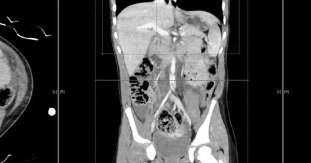

We present a 4-year-old who suffered blunt abdominal trauma leading to Chance fractures to the lumbar spine, bucket-handle injuries to the ileum and descending colon, and an aortic intimal injury...